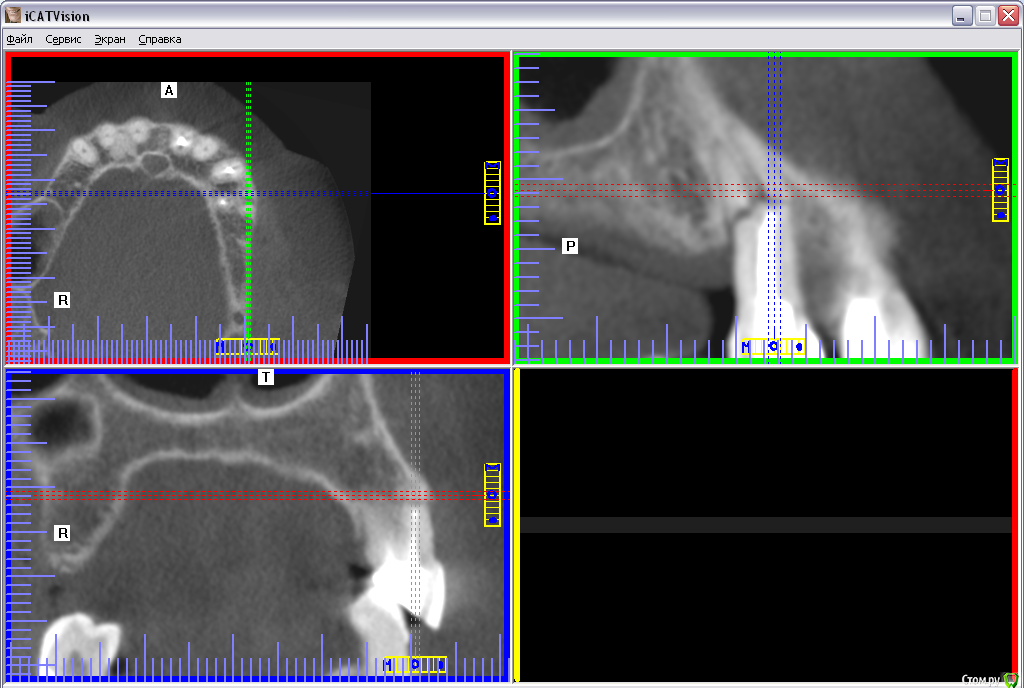

Altai Barnaul Опубликовано 10 декабря, 2017 Поделиться Опубликовано 10 декабря, 2017 Здравствуйте! Что видно на снимке? Каков прогноз? Какие рекомендации? Спасибо. Ссылка на комментарий

Aquarius Опубликовано 11 декабря, 2017 Поделиться Опубликовано 11 декабря, 2017 Прогноз неутешительный 5 Ссылка на комментарий

brg Опубликовано 11 декабря, 2017 Поделиться Опубликовано 11 декабря, 2017 Удалять и протезироваться. Ссылка на комментарий

Altai Barnaul Опубликовано 14 декабря, 2017 Автор Поделиться Опубликовано 14 декабря, 2017 Удалять и протезироваться. Независимо от анамнеза данного зуба? Надеюсь, по снимку видно, что этот зуб уже несколько лет так живёт вместе с чспп. Ссылка на комментарий

red_butler Опубликовано 14 декабря, 2017 Поделиться Опубликовано 14 декабря, 2017 Независимо от анамнеза данного зуба? Надеюсь, по снимку видно, что этот зуб уже несколько лет так живёт вместе с чспп.Анамнез не поможет. По снимку НЕ видно с кем он живёт или спит. Не удалите - выпадет сам 1 Ссылка на комментарий